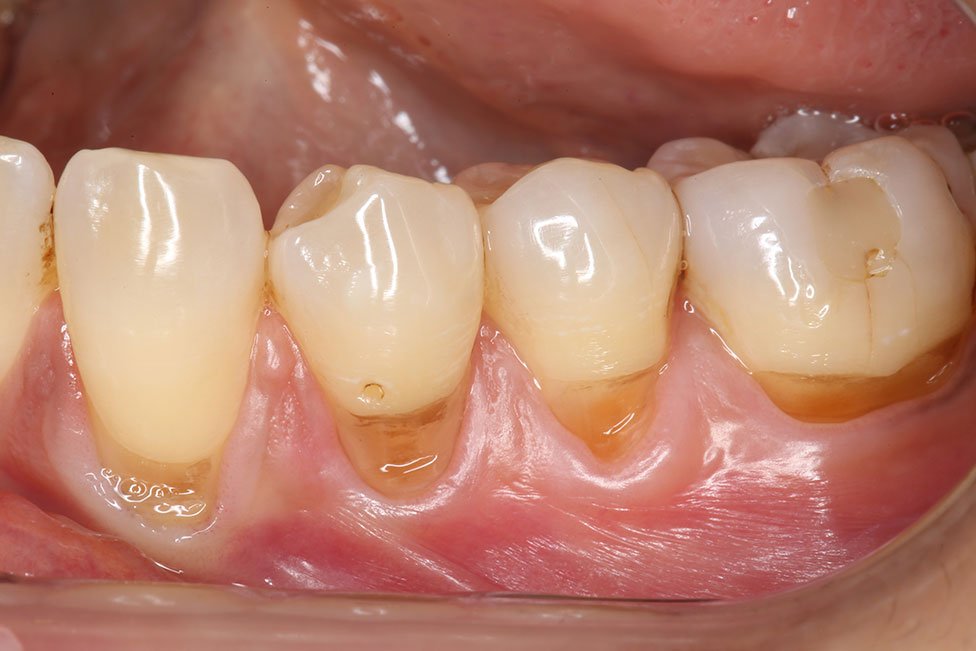

Gallery - Receding Gums

Case 23

Before After